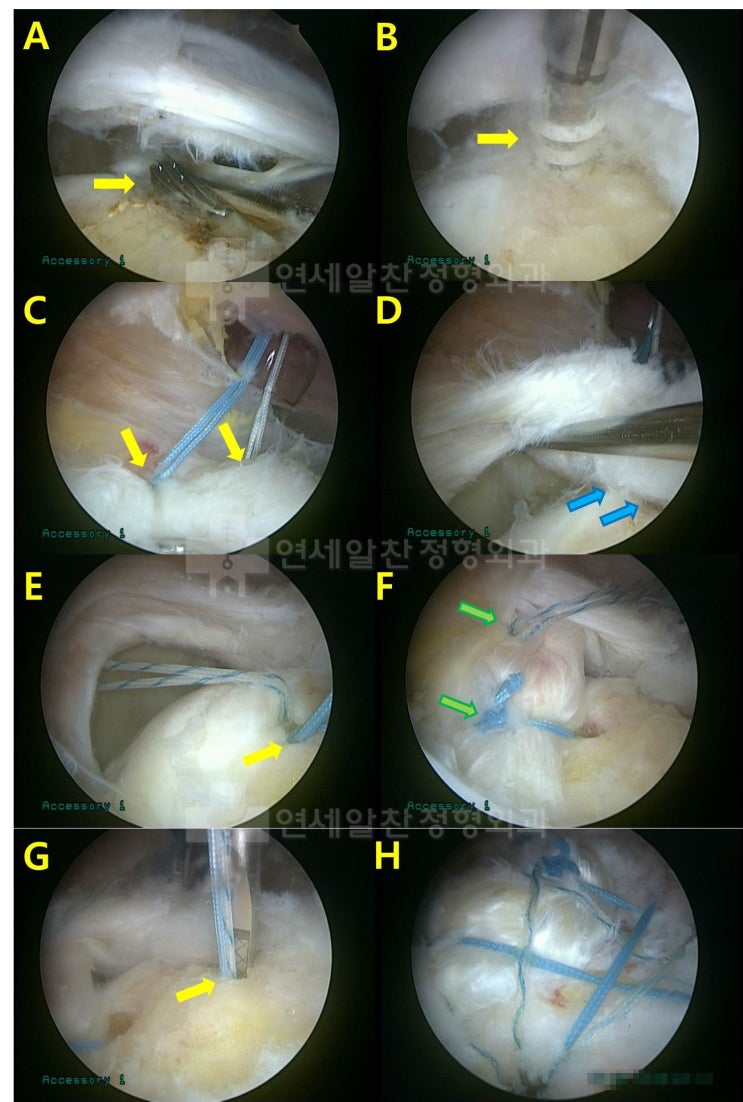

회전근개파열 에서 이열교량형 봉합법 에 대한 고찰

회전근개 파열 을 수술할 경우 봉합법에 대한 문의를 하는 경우가 종종 있다. 회전근개파열 이 있는 경우 ...

2018. 9. 19.